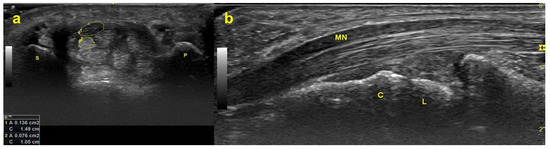

Figure 1. Ultrasonograms captured at the distal wrist crease level. (a) MN (structure enclosed by the upper dotted line) and FDS tendon (structure enclosed by the lower dotted line) in the carpal tunnel on the transverse plane. (b) MN and FDS tendon on the longitudinal plane. Abbreviations: P = pisiform bone; S = scaphoid bone; MN = median nerve; FDS = flexor digitorum superficialis; L = lunate bone; C = capitate bone.

Carpal tunnel syndrome (CTS) is an entrapment neuropathy of the median nerve (MN) inside the carpal tunnel, which is an osteofibrous canal framed by the transcarpal ligament as the roof and the carpal bones as the floor (Figure 1). The MN and nine flexor tendons (the flexor pollicis longus (FPL), the four flexor digitorum superficialis (FDS), and the four flexor digitorum profundus (FDP)) are surrounded and closely connected by subsynovial connective tissue (SSCT), and they travel through the carpal canal together [1] forming a gliding unit [2].